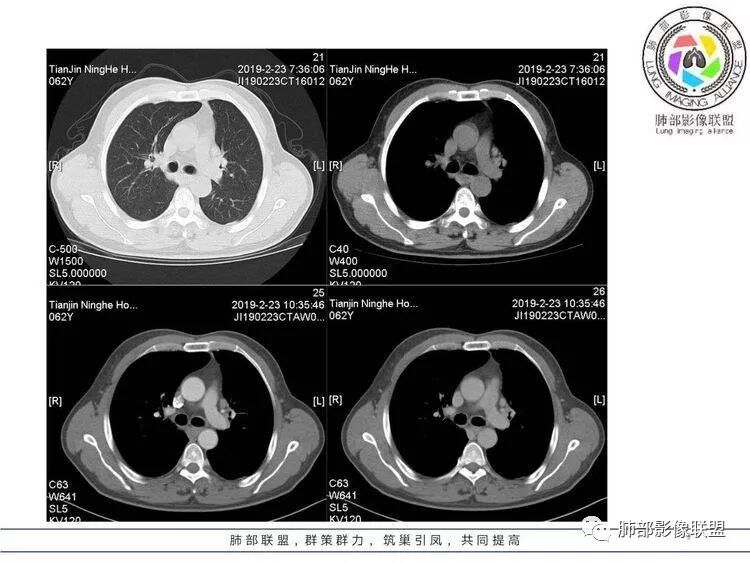

病例资料

王秀仙:左肺上叶肿块,边缘平直收缩,周围可见长索条,轻度强化,密度不均可见低密度坏死,考虑结核。鉴别腺癌。Yiren  Sishui(厶水伊人):晨读:左肺上叶肿块,近胸膜侧光滑,提示符合淋巴回流病变,周围条索,符合肉芽肿性病变,环形强化,中心坏死,考虑结核可能luys:左肺上叶病变,沿支气管分布,边缘平直收缩,周围见长索条,轻度强化,伴边界可见低密度坏死灶。考虑特殊感染。灶内支气管中断,临床以咯血就诊,鉴别肿瘤。博麟:左上胸廓稍缩小,长条索病灶,冠状位似见支气管截断,坏死边界似乎欠清,猜个纤维条索基础上合并瘢痕癌红日东升:晨读:左上叶结块,前缘有粗大索条向前延伸,邻近前联合线明显左移,提示收缩明显。结块边缘平直、收缩;增强结块及索条明显强化,内血管走行自然,坏死灶周围似见三层结构;考虑炎性病变。wonderful:肿块实性边缘光滑  考虑良性病变 合并咯血 。结核或曲霉玫:左肺上叶不规则形软组织密度肿块影,边界清晰,期内密度不均匀,可见坏死,病灶向前呈条索状延伸,矢状位病灶形态欠规整,似有血管中断,考虑恶性病变可能,待除外结核?张帅:左肺上叶病变,病变周围平直,长毛刺,病灶内可见低密度区及支气管征,矢状位提示前段阻塞,病灶内气管不规则扩张,病灶周围有卫星灶,考虑良性病变:结核?我心飞翔:病灶边缘平直,中央可见坏死,周围磨玻璃边界欠清,考虑炎性病变张延军:左肺上叶尖后段肿块,边缘以平直为主,局部膨隆,内见片状坏死区,边界欠清,相应尖后段支气管闭塞,考虑占位并不张,腺癌?建议抗炎治疗后复查丽:左肺上叶病变,边缘平直,并可见长索条,增强后密度不均,可见坏死,首先考虑结核,但重建后支气管走形欠连续,似有截断,恶性待排毛勤香:左肺上叶病灶,边缘平直为主,周围索片影,增强强化不均匀,内有坏死,重建支气管走行欠规则,似有截断,老年男性,需排除恶性(鳞癌?)并阻塞性肺炎可能王萍:左肺上叶团片,大部分边缘平直、凹陷,周围见少许条片模糊影,增强内见坏死区,余区域较均质,其内支气管部分通畅,部分变窄。咯血病史,无发热,考虑肉芽肿性炎可能性大,结核或放线菌等,肿瘤待排THINKER:左上叶,占位,围绕尖后段支气管,U型凹丶平直,长索条,有轻强化及低密度,考虑良性的,首选OP,老年不发热丶咯血,鉴鳞癌、TB飞鹰行动:左肺病灶,有明显的收缩表现,增强后病灶内部可见低密度无强化区,病灶内支气管轻度扩张呈串珠状改变,支持炎性病变,结核可能性大。杨泽锋:支持炎性病变伴小脓腔形成,但不支持结核,因为病灶内可以可见血管影THINKER:问一下各位老师:这个给的强化,是肺动末期丶主动脉未期`延迟期?大雄:老年男性,左肺上叶前段条片状实变影伴周围长条索,境界清晰,边缘部分锐利光滑、部分毛糙,增强可见中央局部坏死,周围无强化区轻中度均匀强化,无钙化,无明显卫星灶,无胸膜明显牵拉凹陷。病灶整体收缩力有,张力不明显,肿瘤概率小。临床无明显急性感染症状,倾向于慢性增生性炎症,累及段支气管,引起了咯血。结核多见,但慢性结核肉芽肿一般强化没这么明显。OP不除外。老年男性如果有长期吸烟史,鳞癌不能完全排除,鳞癌的坏死强化都符合,鳞癌收缩力也不强,形态更是变化无常左手:老年男性,咯血,左肺上叶长条样结节,边缘见牵拉影,支气管堵塞,病灶内见坏死,坏死边缘偏清,考虑鳞癌,鉴别结核宇宙星空:支持恶性。鳞癌可能性大。支气管截断及空泡征

Shelia:考虑机化性肺炎伴小脓肿形成?炎性肌纤维母细胞瘤?鉴别癌食客:左肺上叶病灶,边缘平直,周围条片影,增强内见坏死区,内支气管部分通畅,咯血病史,无发热,考虑结核,肿瘤不除外。管洪林:左肺上叶尖后段病变,整体边缘平直,部分稍收缩,临近长索条影,胸膜缘可见轻度牵拉,增强后整体强化明显,其内可见低密度类圆形坏死区,边界清,首先考虑op并小脓肿形成,但部分层面显示小支气管受阻,是否层面原因?管洪林:若是支气管阻塞,鳞癌作为鉴别雪上一枝蒿(陈显静):他这个动脉期是不是不是很明显啊,觉得跟静脉期差不多,强化值也不好分辨?徐超:左肺上叶实变,边缘平直,周围无磨玻璃及卫星灶,病灶内坏死,强化后边界清楚,无壁结节,余病灶轻中度均匀强化(对比肌肉),增强后血管显影清楚自然,未见破坏边缘毛糙,血管旁条形无强化区(粘液?)整体符合炎性特点,炎性假瘤或op可能,伴小脓肿;结核放后面待排(结核病灶内血管完好,边缘清楚,且强化近中度,不是很合理,肉芽肿到也可以)。红日东升:平扫和强化窗宽窗位不一样良孑:左上实变,有平直及长毛刺,其内支气管牵拉性扩张,提示收缩力较强,无卫星灶,强化不支持TB,均匀强化,无分叶不支持鳞癌,影像上提示慢性进程,考虑OP并脓肿,鉴别炎肌母。